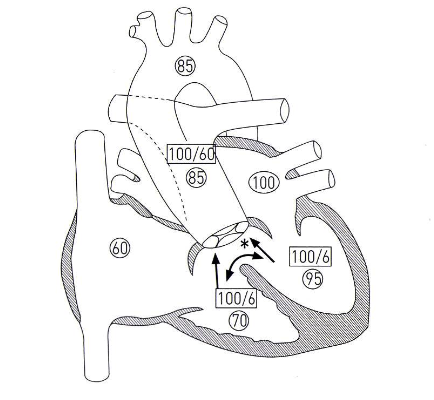

4가지 해부학적 이상을 특징으로 함:

① 심실중격결손(VSD)

② 폐동맥 협착(Pulmonary Stenosis / RVOT)

③ 대동맥 우위(Overriding Aorta)

④ 우심실 비대(RV Hypertrophy)